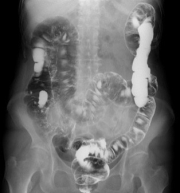

X線透視検査

X線透視撮影装置でX線を連続的に使用しリアルタイムで状態を観察し、撮影を行います。

造影剤を使用した消化管検査(胃透視、注腸造影)や嚥下造影をはじめとし、脱臼や骨折の整復・固定、内視鏡と併用した治療も行います。

主な検査

上部消化管検査

下部消化管検査